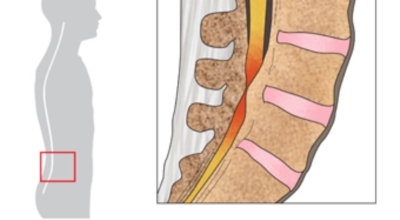

요추관 협착증은 척추 내 신경이 지나가는 통로가 좁아지는 현상으로 기인해서 신경이 눌리면서 이에 따른 여러가지 증상을 유발하는 질환을 의미해요.

일상생활에서 허리 척추에 무리를 주는 행위가 반복적으로 행해질 경우 허리 뿐만 아니라 주변 근육과 인대의 퇴행이 빨라질 수 밖에 없어요. 허리 협착증의 경우 허리를 뒤로 젖히면 통증이 심하게 나타나지만 허리를 굽히면 척추관이 일시적으로 넓어지는 영향으로 통증이 줄기 때문에 자연스럽게 아프지 않은 자세를 하다보니 허리가 점점 굽는 자세를 만들 수 있어요.